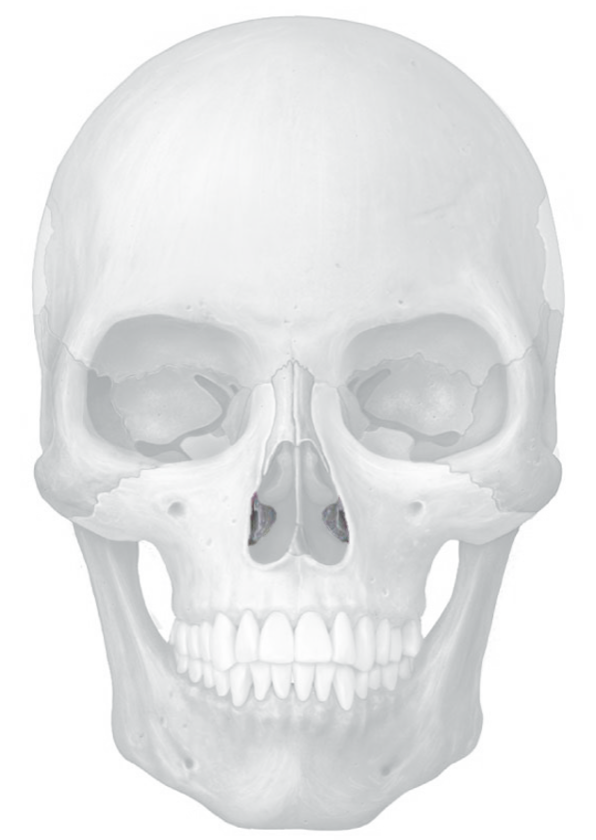

cranial bone

encloses brain

attachment site for head and neck muscles

facial bones

form framework of face and contains cavities for special senses (taste,smell,hear)

provide openings for food and air

anchor facial muscle

frontal bone

Parietal bone

temporal bones

occipital bone

Occipital condyles

two knobs on occipital bone that connects skull to first vertebra

sphenoid bone

ethmoid bone

mandible

maxillae bones

zygomatic bones

Nasal bone

vomer

lacrimal bones

palatine bones

inferior nasal conchae